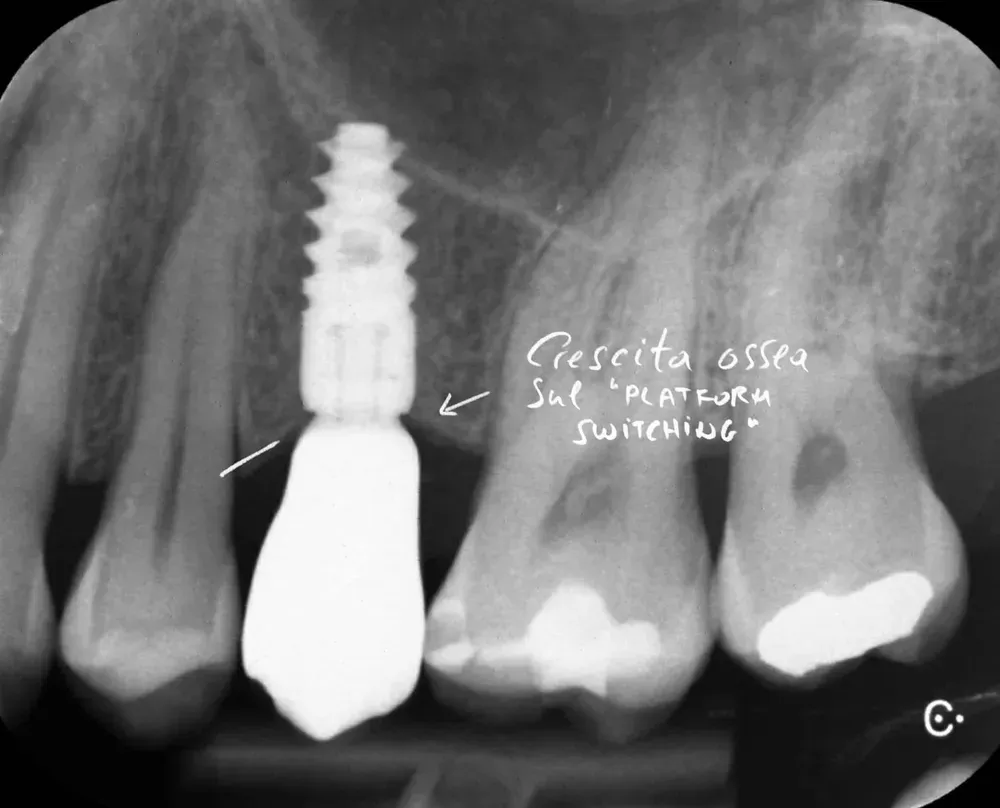

Gli impianti transmucosi devono essere posizionati transmucosi, soprattutto se hanno connessioni non particolarmente “sigillanti”. Usati in tal guisa, sono perfetti. Le immagini che seguono dimostrano che i transmucosi, se posizionati al giusto livello verticale, causano ZERO riassorbimento della cresta ossea.

Platform switching: un’idea ottima

Il platform switching — l’uso di un abutment di diametro inferiore rispetto alla piattaforma implantare — ha basi biologiche solide. L’effetto è triplice. Il concetto è stato pubblicato da Lazzara e Porter nel 2006 (https://pubmed.ncbi.nlm.nih.gov/16515092/).

Primo: lo spostamento laterale della giunzione impianto-abutment allontana l’infiltrato infiammatorio dall’osso marginale . Secondo: le fibre collagene attorno agli abutment con platform switching si organizzano in modo circolare, stabilizzando il connettivo e proteggendo l’osso sottostante — come dimostrato istologicamente da Rodríguez e collaboratori su impianti conici nell’uomo (https://doi.org/10.11607/prd.2580) Terzo: la concentrazione dello stress meccanico si sposta dall’osso cervicale verso l’impianto stesso, anche se con un potenziale aumento dello stress sulla vite (https://doi.org/10.1111/j.1600-0501.2007.01398.x).

Sul piano clinico, Duque e colleghi hanno riportato una prevalenza di peri-implantite del 6,6% per impianti con platform switching contro il 15,6% per impianti convenzionali (https://doi.org/10.1590/1807-3107bor-2016.vol30.0005). Le revisioni sistematiche confermano una maggiore stabilità dell’osso crestale attorno agli impianti platform-switched (vedi per esempio (https://doi.org/10.1111/clr.12339).